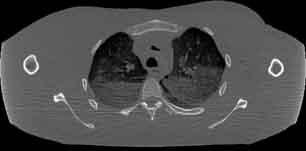

Visible Human male: Sectio transversalis 1358

CT